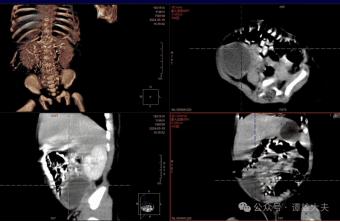

小宝宝诞生到这个世界,本是一件家里的大喜事,但这一家人却有些高兴不起来。因为,产前B超已经提示,胎儿腹部有巨大肿块,出生后体检也发现该女婴腹部能摸到质地较硬的包块,约有6厘米直径。宝宝第28天,家人立即带着宝宝来到南华附二就诊,入住儿童普外科。进行CT检查提示,考虑腹腔肿块,而且不能排除恶性肿瘤,需要手术治疗。

手术紧张而有序地进行。术中发现腹腔肿块来源于宝宝右侧卵巢,诊断考虑卵巢畸胎瘤,并且已经扭转坏死。分离结扎肿瘤的血管,将肿瘤放置于脐部穿刺鞘的位置,抽吸肿瘤囊液,最后将肿瘤从脐部穿刺鞘的切口取出。手术顺利,术中出血仅约2ml。